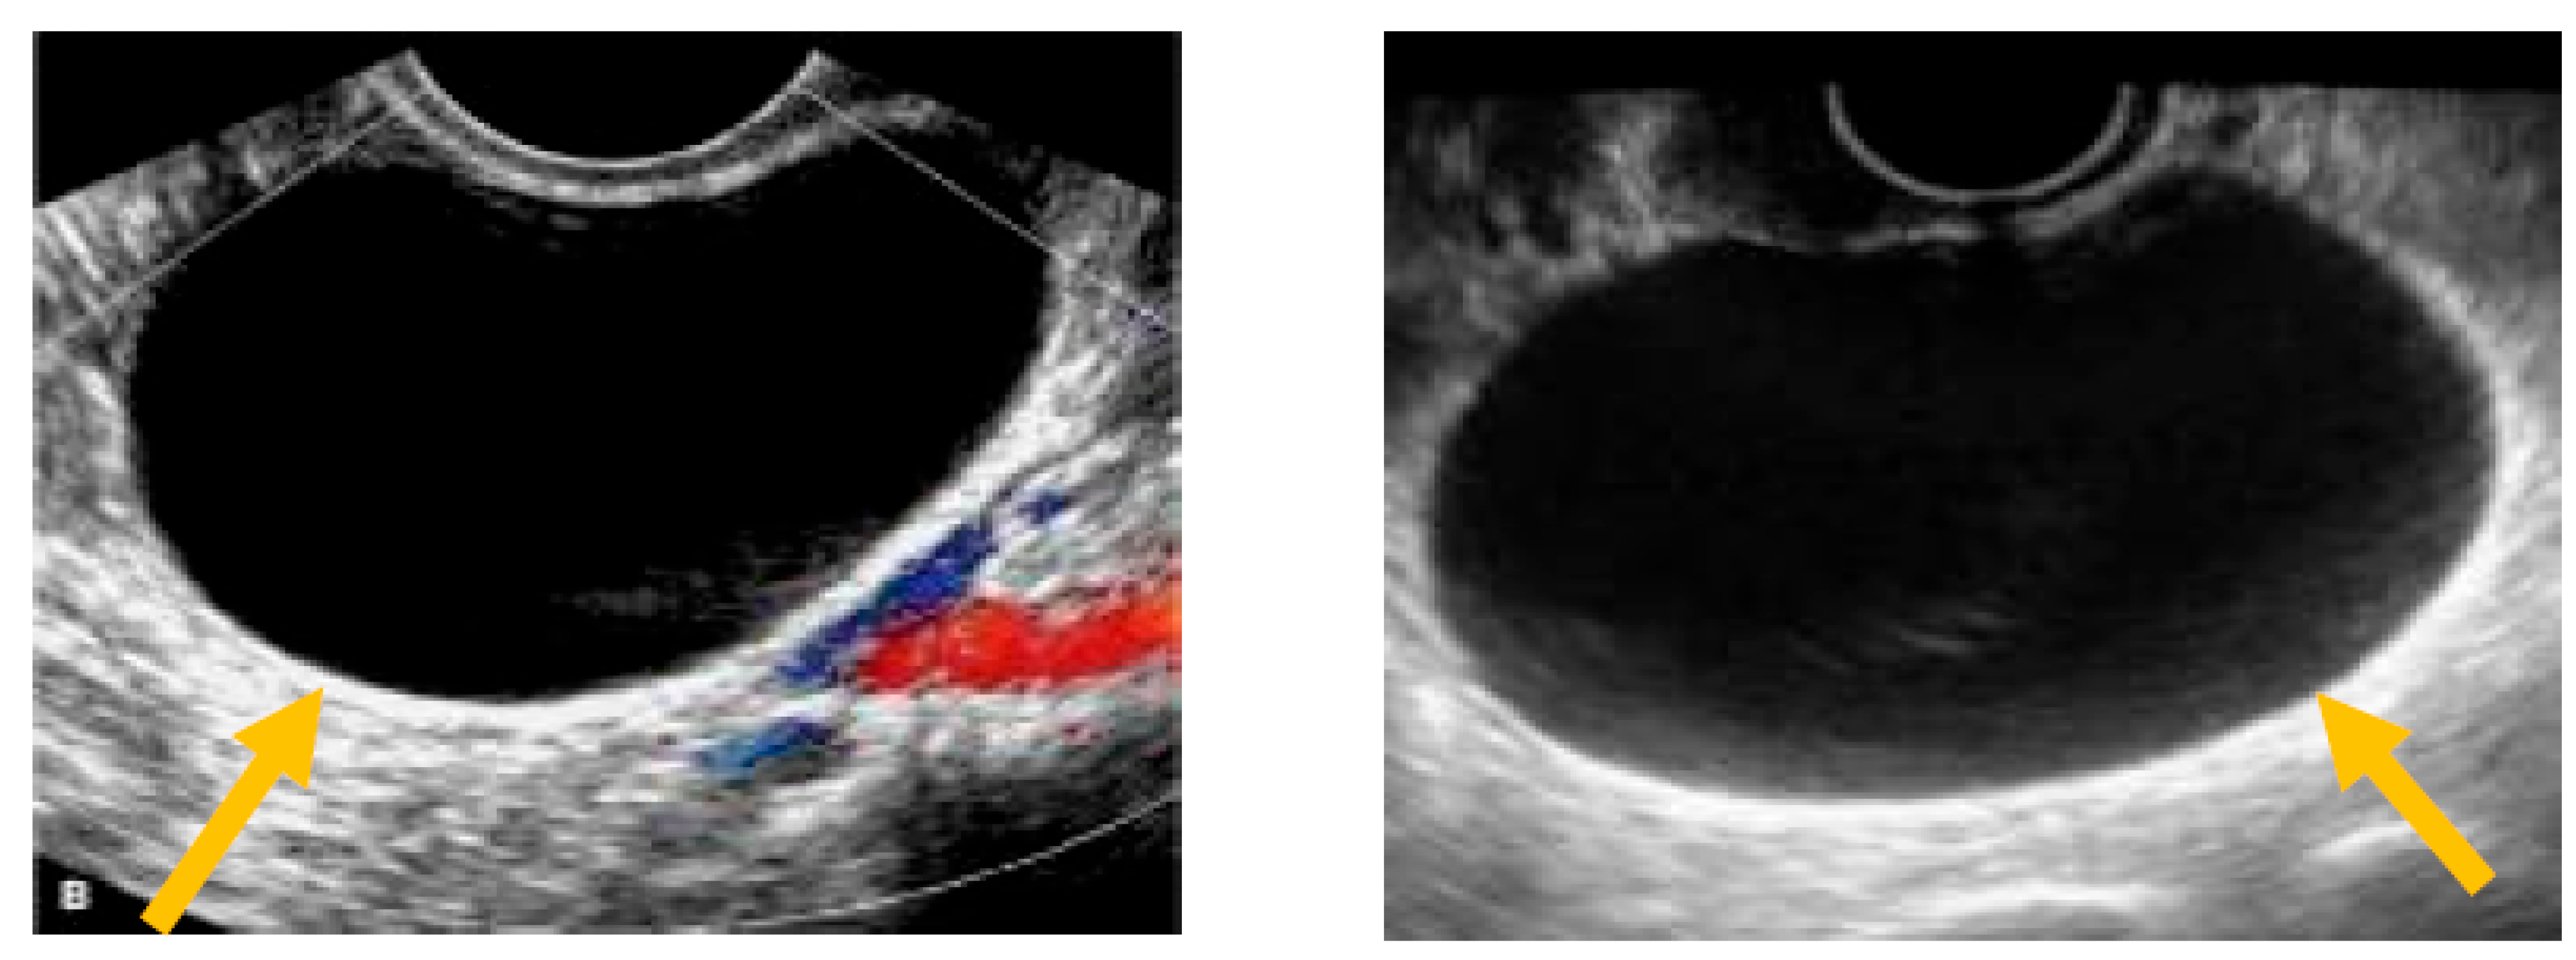

The existence of irregular solid tumors, ascites, at least four papillary structures, an irregular multilocular-solid tumor (diameter at least 10 cm), and very strong blood flow on a color Doppler assessment are malignant indicators, whereas a unilocular cyst, the presence of solid components (max diameter < 7 mm), the presence of an acoustic shadow, a smooth multilocular tumor (max diameter < 10 cm), and the absence of detectable blood flow on the Doppler predispose for the presence of a benign mass [24] (Figure 1, Figure 2 and Figure 3).

Figure 1.

Unilocular cyst. (Yellow arrows indicate the presence of a cyst with one locule, no solid components and no papillary projections, while blood flow is absent).